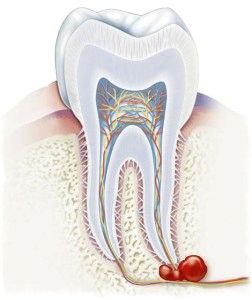

Зовні кіста виглядає як порожнину овальної або каплевидної форми, покритої щільною оболонкою. Внутрішній вміст цього новоутворення - гнійна рідина жовтуватого відтінку.

Зовнішній шар кісти обмежений клітинами сполучної тканини. Сама ж порожнину вистелена плоским багатошаровим епітелієм. Розміри варіюються від декількох міліметрів до двох сантиметрів.

- Радикулярную або кореневу кісту зуба. Це найбільш поширений вид даної патології. Причиною служить запалення періодонта, що протікає по хронічного типу. Периодонт - це спеціальна сполучна тканина, що дозволяє утримувати зуб в кістках щелепи.